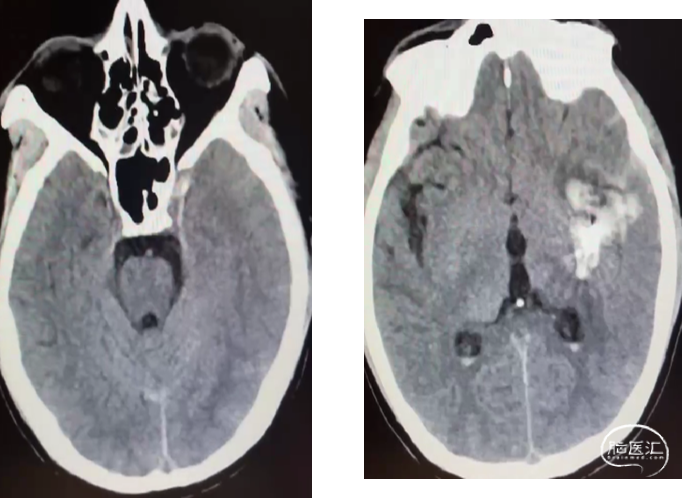

术后即刻造影畸形血管团不显影

术后CT复查,少量出血,癫痫发作,继续控压、抗癫痫等治疗